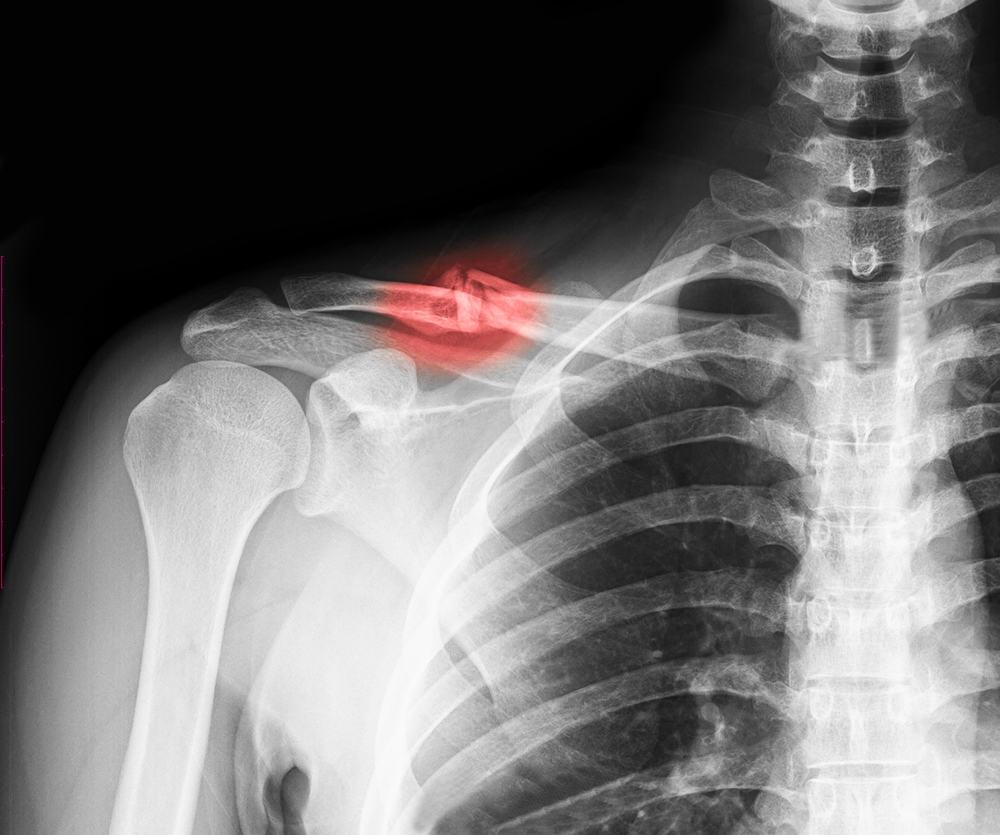

Jika diduga bahwa Anda memiliki patah tulang selangka, dokter akan merekomendasikan sinar-X dari bahu untuk membuat diagnosis lebih lanjut.

Sinar-X dapat menampilkan gambar dari fraktur tulang selangka terkait lokasi dan seberapa parah kondisinya atau jika ada tulang lainnya yang rusak.

Dalam beberapa kasus, jika dokter perlu melihat fraktur secara lebih detail, computerized tomography (CT) scan akan dilakukan.